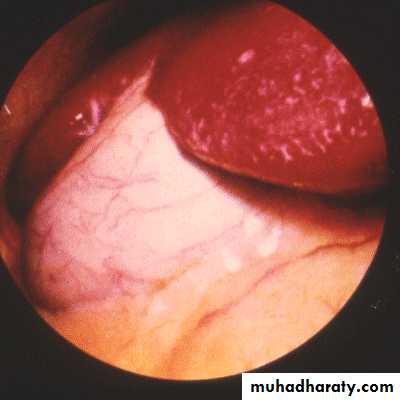

• Laparoscopy

Gall bladder beneath the peritoneum